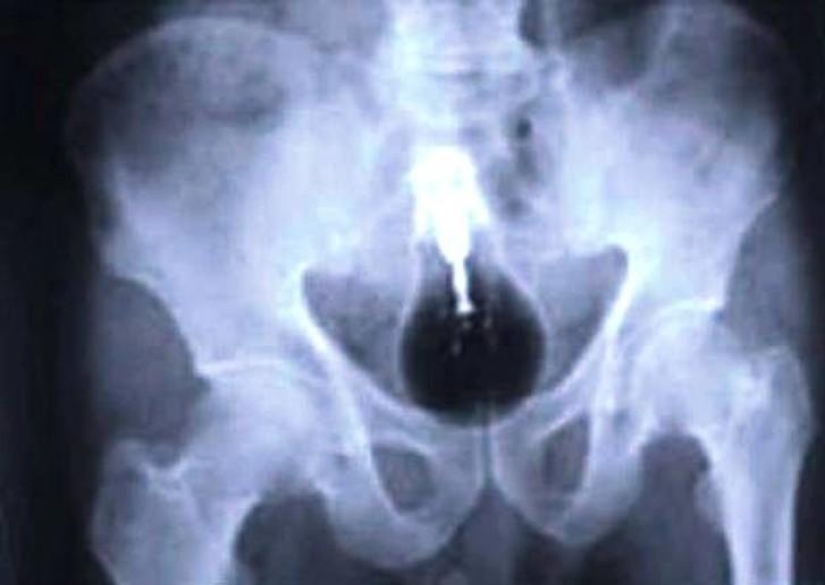

15. Bombilla.